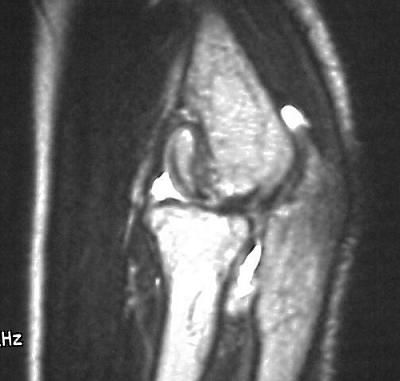

MRI shows an osteochondral sequestrum of the anterior capitellum:

Treatment options? Do nothing, Open reduction and bone graft, sequestrum excision or radial head excision. In this case, at surgery, the loose articular fragment was too thin to allow reliable fixation, and was simply excised.